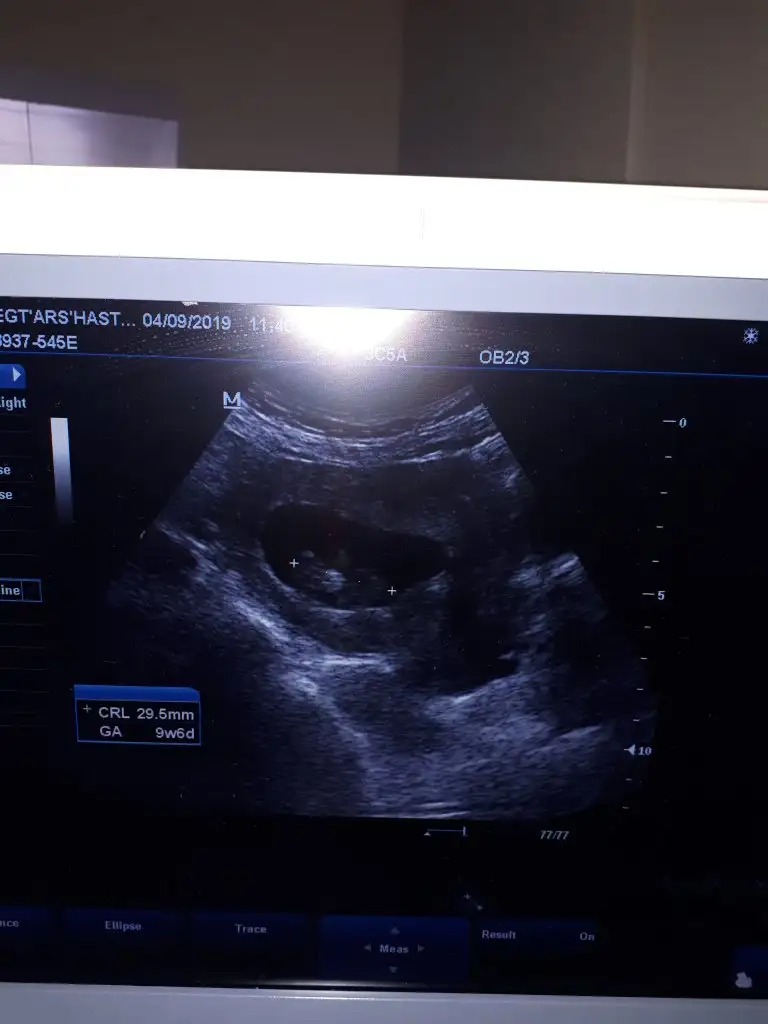

10 haftalık usg nub iki tarafa benzer şimdilik kız gibi ama degişebilir 11 yada 12 hafta usg olmalı nub içinMerhaba hanimlar,bizde 10. Haftanin içindeyiz karindan usg yorumlayabilir misiniz acaba?